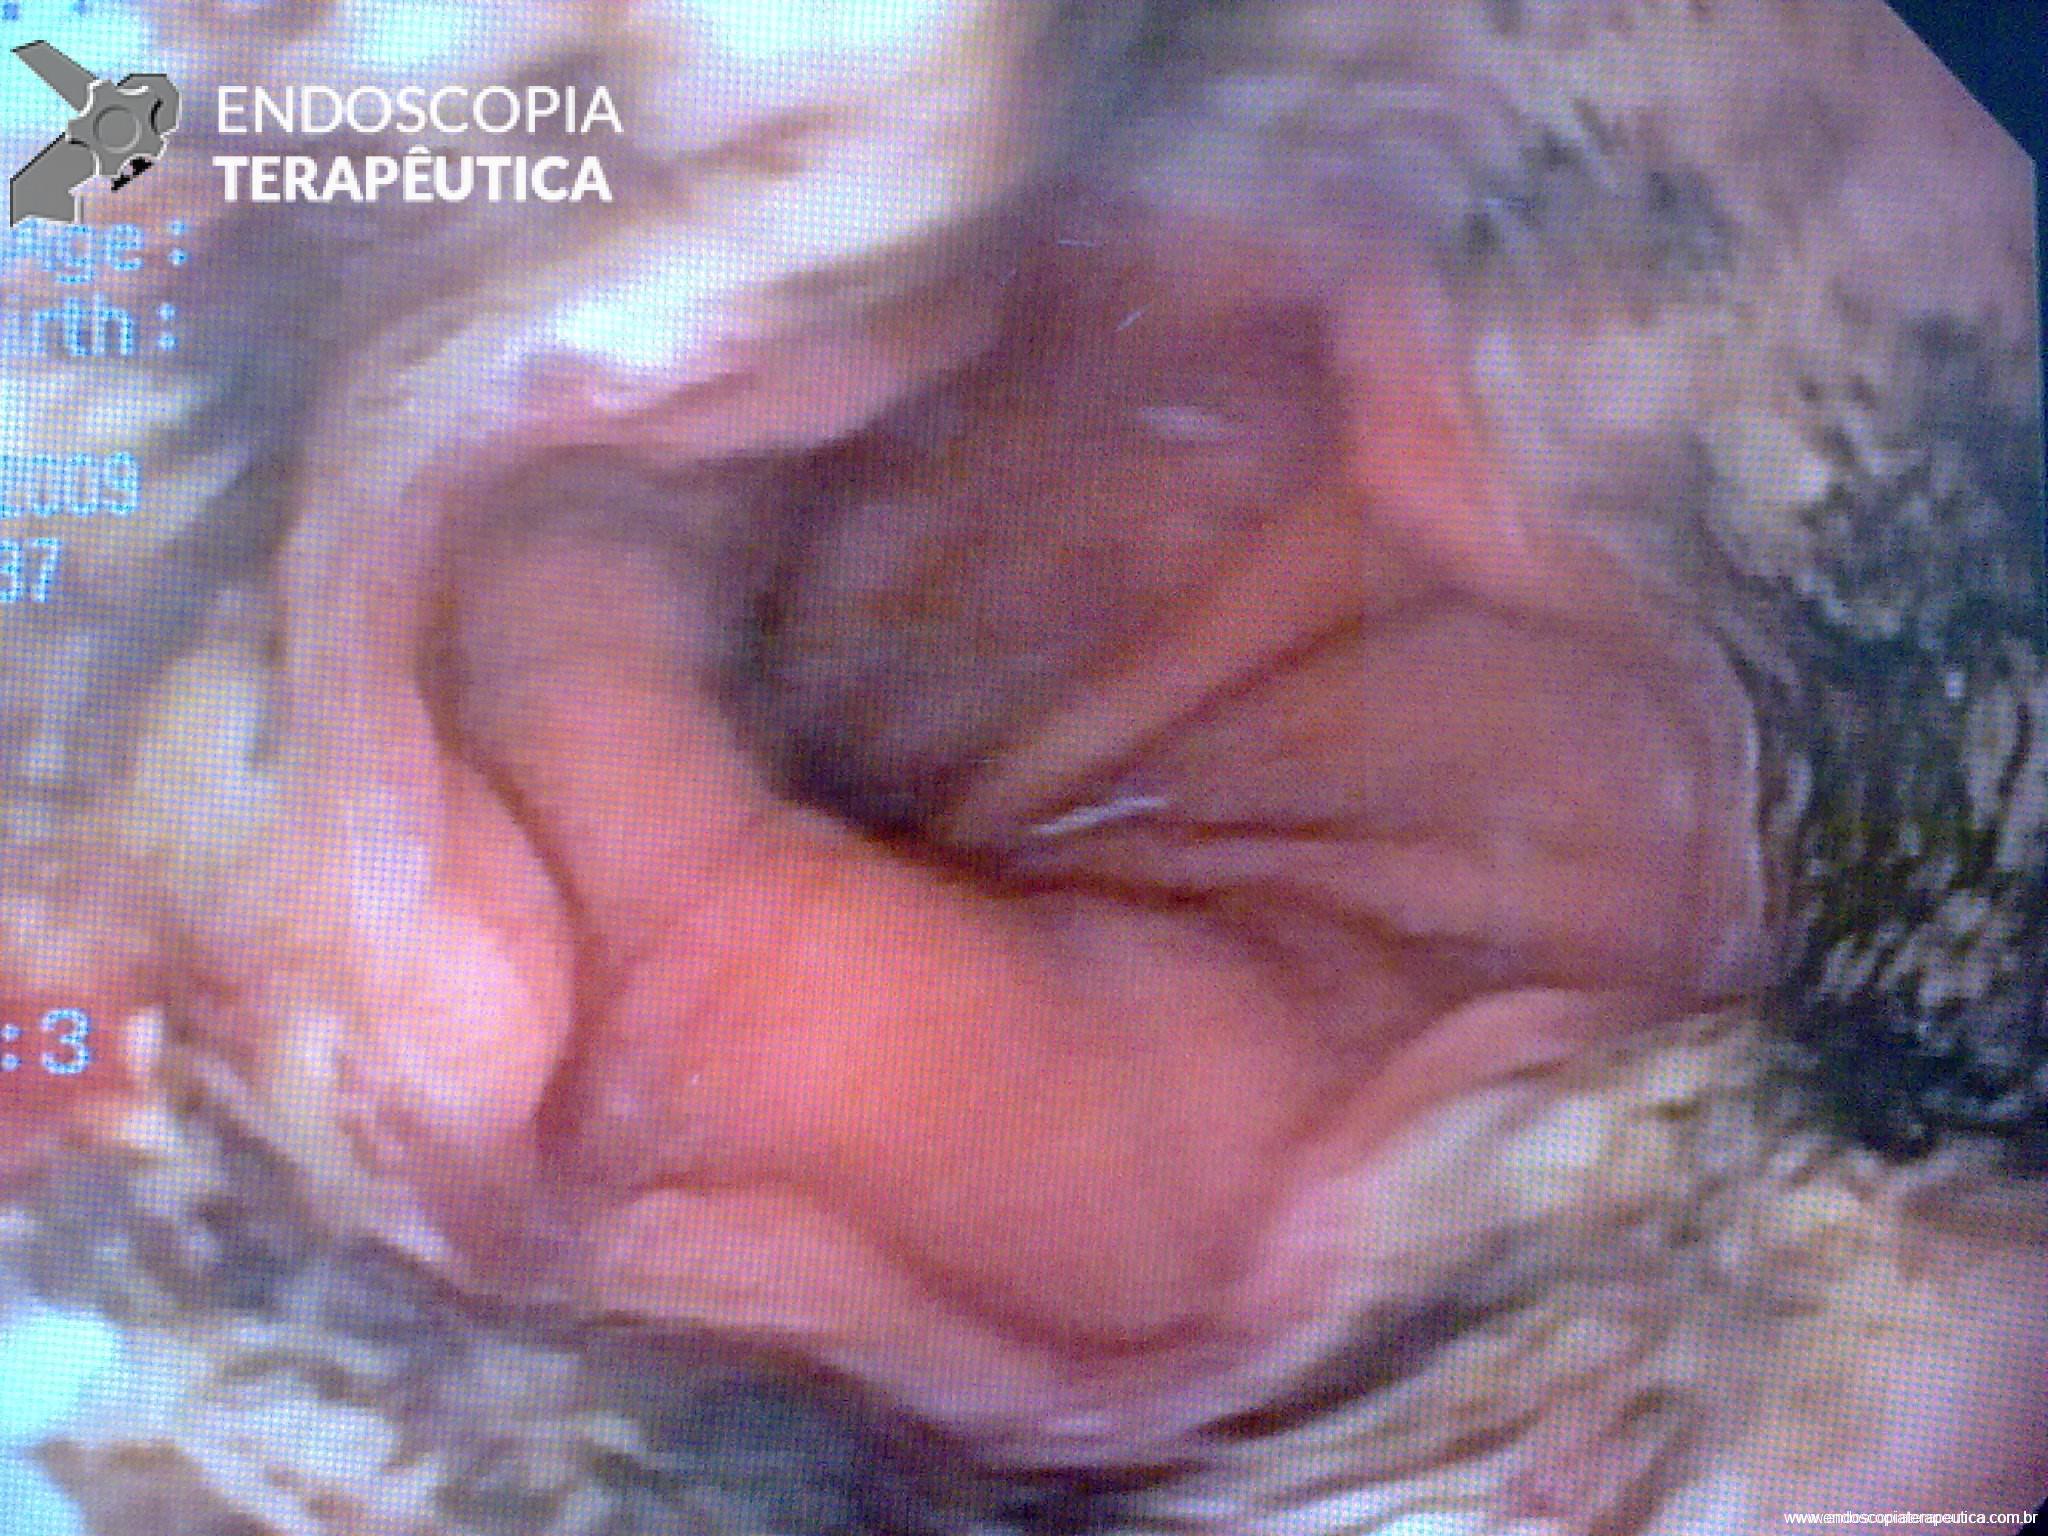

Esôfago Negro